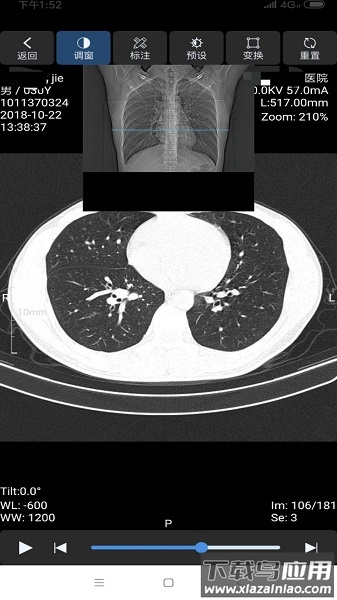

这是飞图影像云平台对应的移动端管理工具。医生使用此应用,能够快速完成原始数据的传输,并在线进行影像查看、多角度调整、测量分析等多项操作。

功能全面,操作实用——支持窗宽窗位调整、测量、角度计算、CT值读取、图像旋转等专业操作;

原始数据,画质高清——采用DICOM标准格式,完整保留影像细节与信息,确保诊断精度;